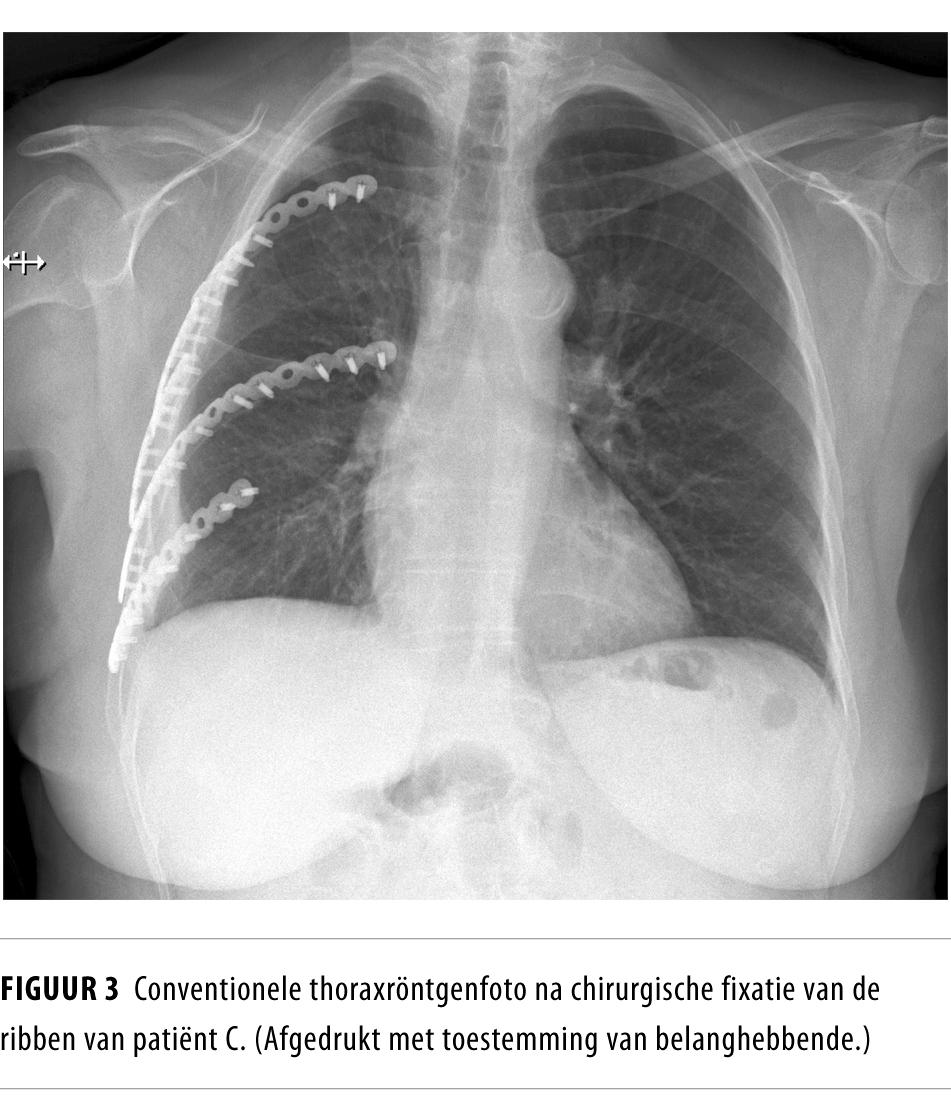

Er werd een epidurale katheter geplaatst voor pijnstilling. Vanwege de fladderthorax fixeerden we ribben 4-8 direct operatief met behulp van platen en schroeven (MatrixRIB fixation systems, DePuy-Synthes, VS) (figuur 3). Direct na de operatie kon patiënte worden gedetubeerd. Op dag 2 na opname werd zij overgeplaatst naar de verpleegafdeling, waar de thoraxdrain werd verwijderd. De epidurale katheter werd op dag 5 postoperatief verwijderd. De enkelbreuk behandelden we met gipsverband. Ook de clavicula- en bekkenfracturen behandelden we conservatief.

Operatieve ribfixatie Bij sommige patiënten kan worden overgegaan tot operatieve fixatie van ribfracturen, zoals bij patiënt C. Zij had een fladderthorax met een paradoxaal bewegend deel van de thoraxwand bij inspiratie. Dit gebeurt wanneer er 3 of meer ribben op meerdere plaatsen zijn gebroken of wanneer er forse distractie is van enkelvoudige fracturen. Door de drukverlaging bij inspiratie ontstaat een intrekking waardoor de functionele pulmonale capaciteit vermindert.